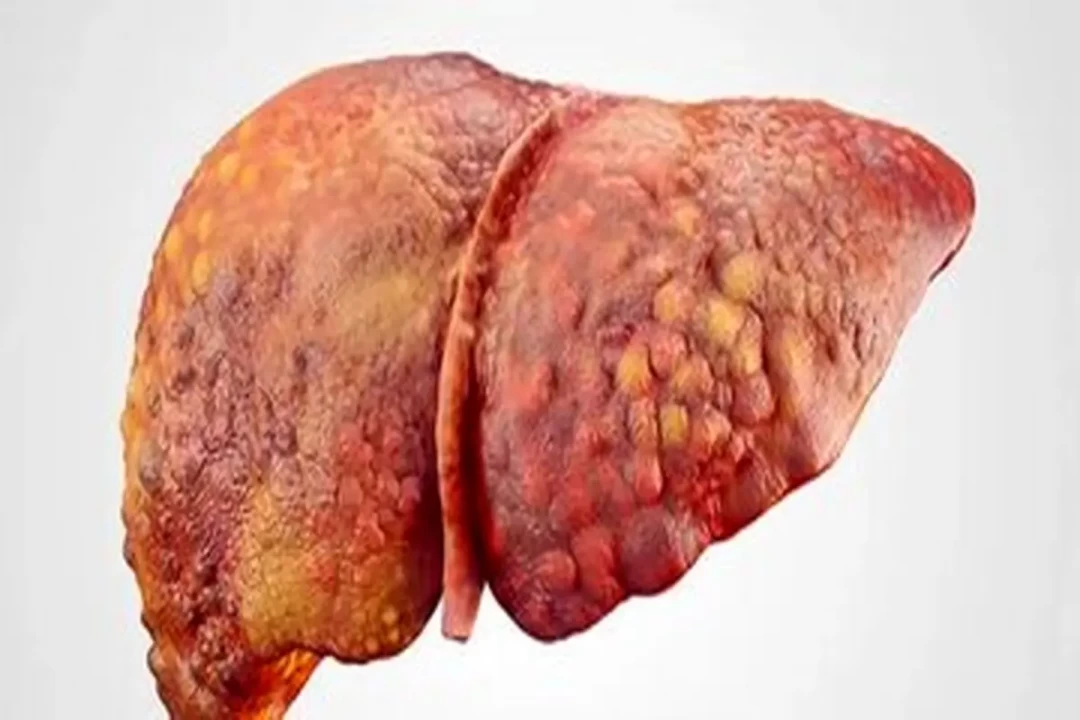

به گزارش پارسینه به نقل از ایسنا، بیماری کبد چرب یا همان استئاتوز کبدی، وضعیتی است که در آن چربی اضافی در کبد تجمع میکند و در افراد چاق یا دارای اضافه وزن، بسیار شایع است.

در هر دو نوع بیماری کبد چرب، چربی اضافی میتواند به کبد آسیب برساند و منجر به بیماری های جدی تری شود که شامل هپاتیت غیر الکلی که در آن کبد، ملتهب و آسیب دیده میشود و سیروز به عنوان یک بیماری مزمن کبدی که در آن بافت اصلی کبد تغییر شکل داده و کارایی خود را از دست می دهد، میشود.

لازم به ذکر است بیماری کبد چرب که با تجمع چربی در کبد مشخص میشود، یک مشکل بهداشتی رو به رشد در سراسر جهان است در حالی که تغییرات سبک زندگی مانند رژیم غذایی و مدیریت وزن در بهبود آن بسیار مهم هستند و ورزش نیز نقش بسیار پر رنگ و مهمی در مدیریت و احتمالا معکوس کردن روند رشد این بیماری ایفا میکند.